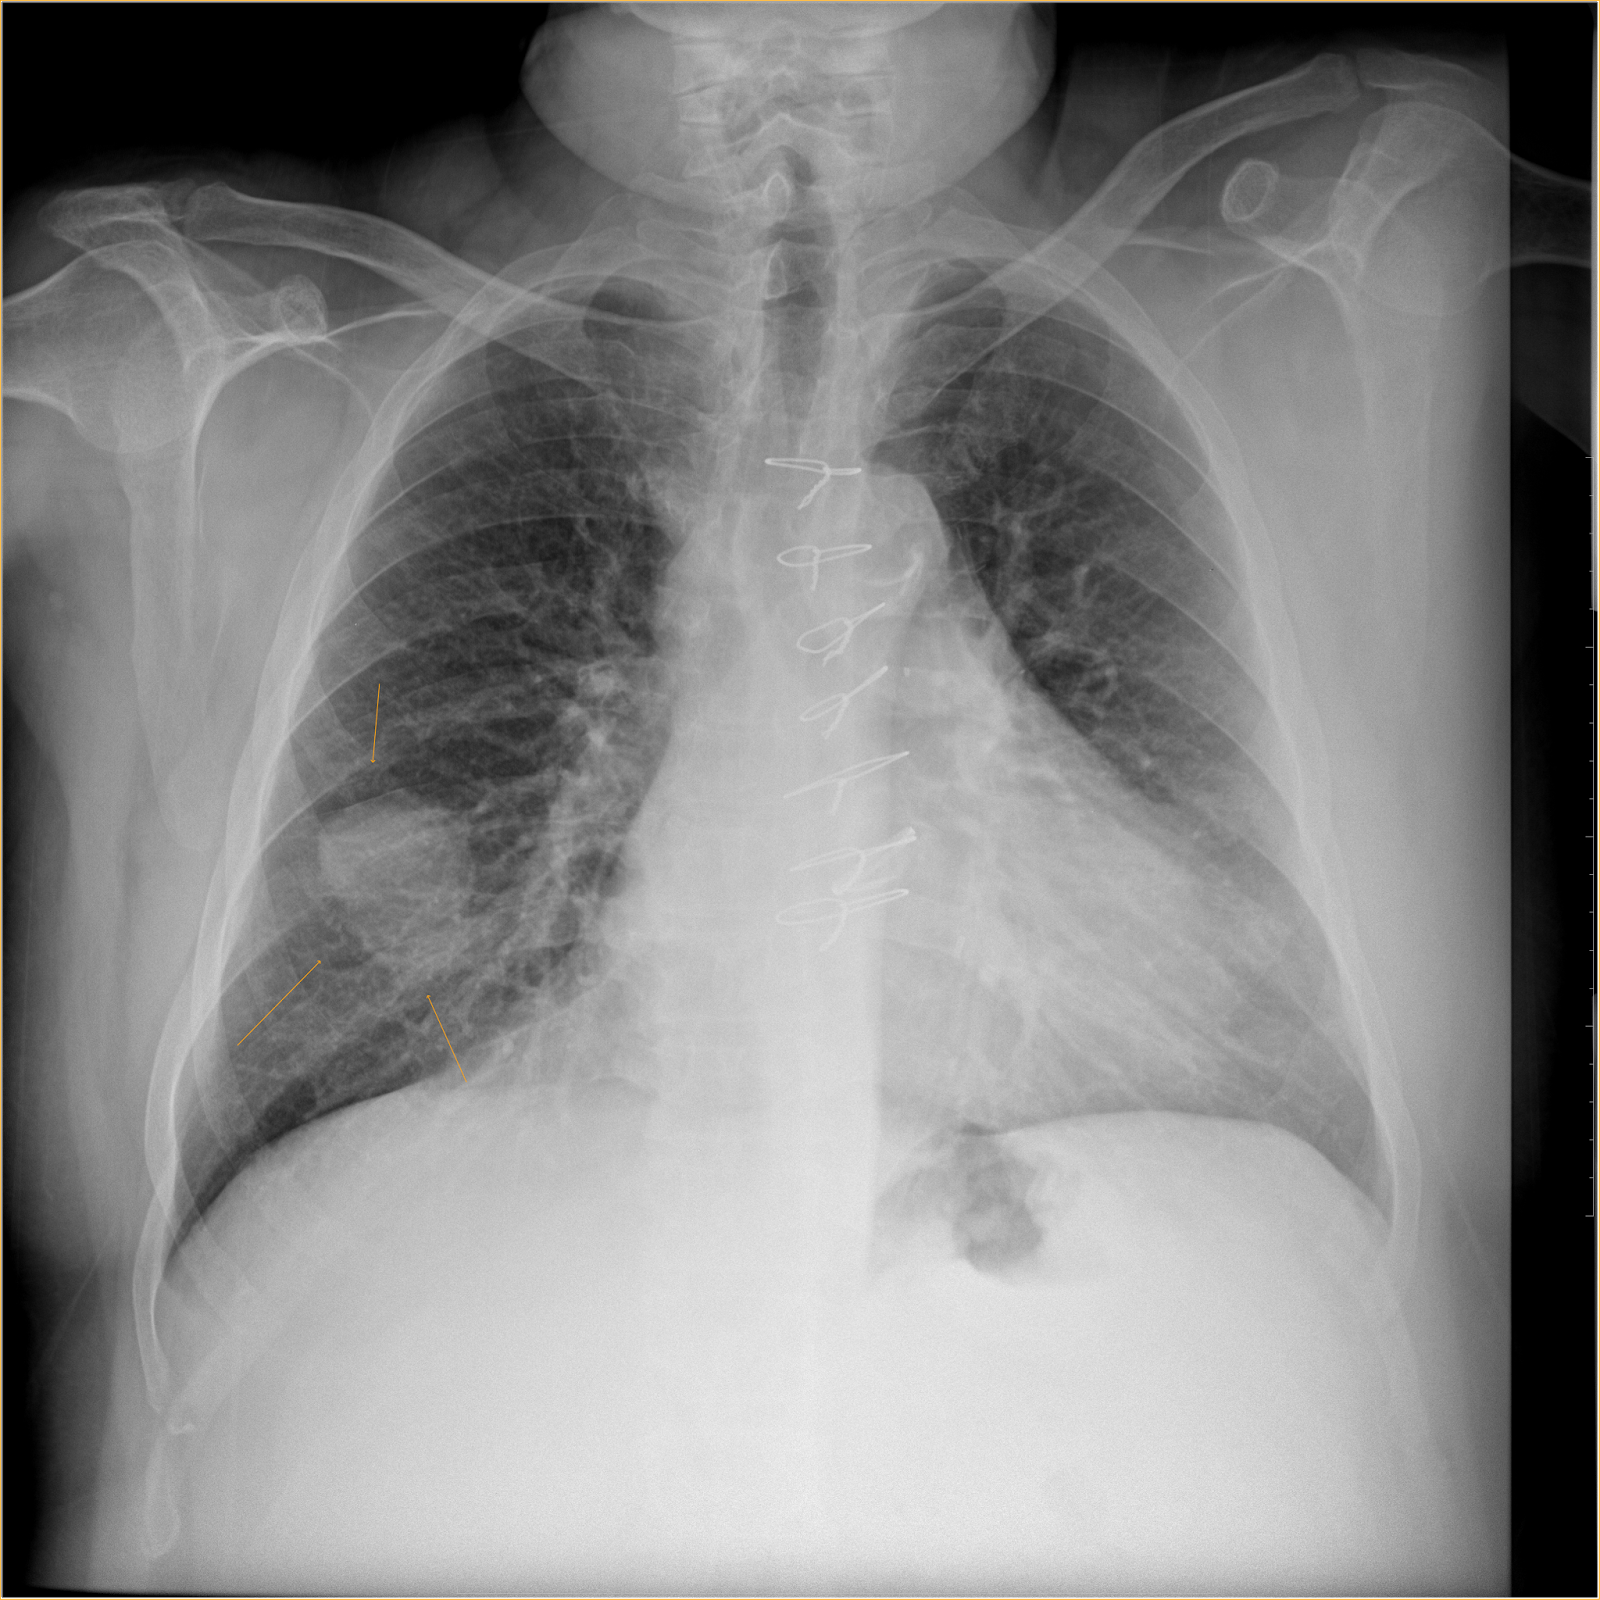

His procedure was completed by Dr. Joseph Romero, BayCare Pulmonologist. He is the lead physician at the lung nodule clinic, where biopsies are done to nodules, lesions and masses to see if they are cancerous.

For the past two years, Morton Plant has used an ION machine to catch lung cancer early. Lung cancer cases that may have only been treatable in the past are now curable.

The machine uses a camera that is inserted down a person's mouth, through their tracheal tube, and then into their lungs.

Once there, Dr. Romero guides the camera with controls to the problem spots, already identified through scans.

"The virtual model here that is created by the CAT scan essentially almost perfectly matches what we see in real life," said Dr. Michael Kayatta, Cardiothoracic Surgeon.

Once the biopsy results came back on Parker's nodule, showing it was cancerous, Dr. Kayatta was the one to surgically remove the spot.